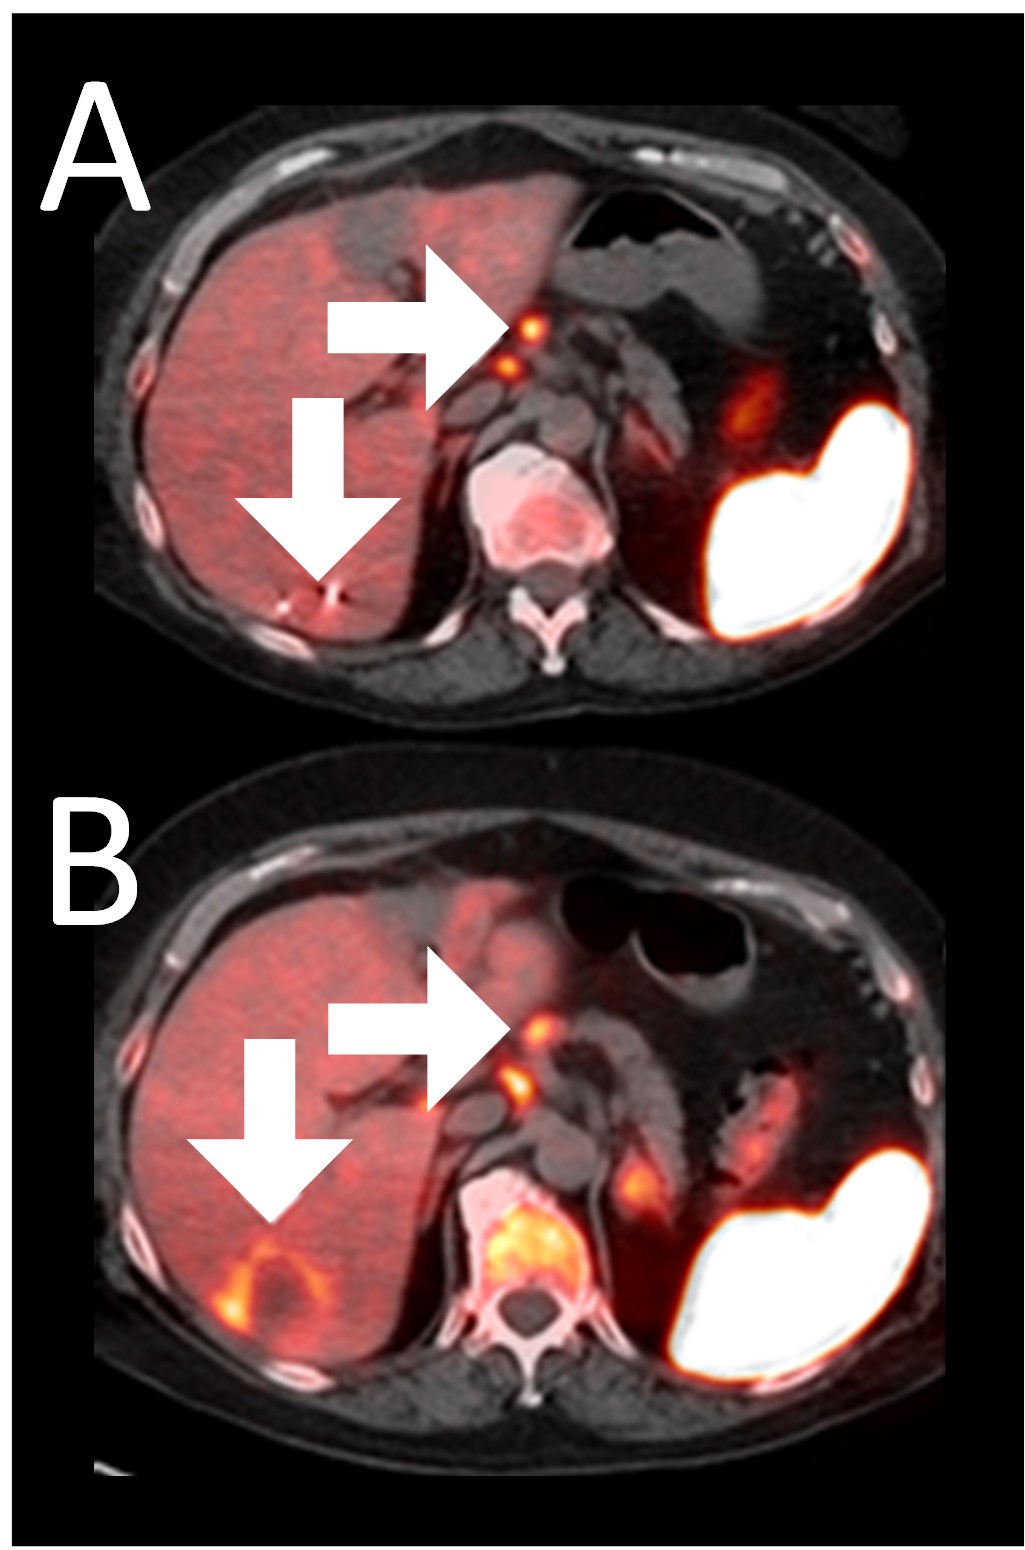

A 64-year-old woman with ER+/PR-/HER2- metastatic breast cancer, heavily pre-treated with 8 prior lines of therapy, including the antibody-drug conjugate Trodelvy, remains alive 25 months post-enrollment. At baseline, presented with hepatic metastasis.

Before BriaCell Treatment Image A: A liver metastasis (lower arrow) is “cold,” indicating minimal to no CD8+ cytotoxic T cells in the tumor while enlarged lymph nodes (upper arrow) show moderate uptake.

After BriaCell Treatment Image B: Swelling (induration) around the metastasis (lower arrow) demonstrates the liver metastasis has become “hot”, indicating marked CD8+ cytotoxic T cell infiltration while further lymph node enlargement is consistent with increased activity (upper arrow) indicating increased CD8+ T cells.

Example 3 Images (Patient 15-006):Combined MRI and CD8 ImmunoPET images Pre (A) and Post (B) Bria-IMT treatment